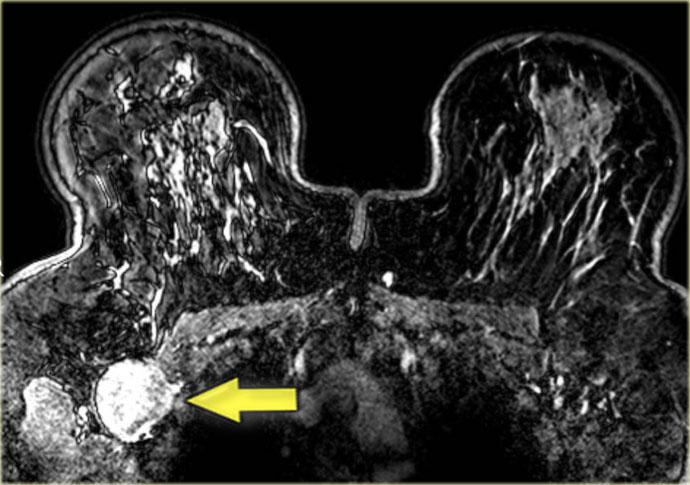

Bên trái là ví dụ điển hình của u xơ tuyến: một tổn thương hình tròn, bờ nhẵn

với một số vùng đen hoặc xám ở bên trong, đó là các vách ngăn không ngấm thuốc.

Tổn thương này có đường cong động học loại 1.

Ngoài cùng bên trái là một ví dụ khác về u xơ tuyến với các vách ngăn không ngấm thuốc rõ ràng.

Các vách ngăn này cũng có thể quan sát thấy trên tiêu bản đại thể bệnh lý.